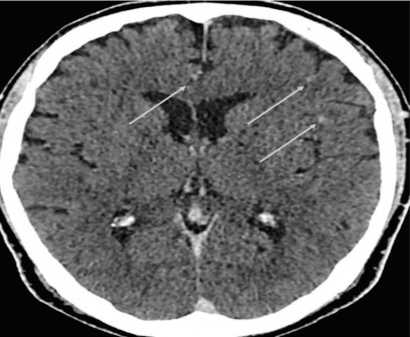

снижение объема мочевого пузыря до 50 мл, утолще ние его стенок до 10мм.По данным компьютерной то мографии (КТ) органов дыхания картина диссемини рованного туберкулеза легких (рис. 1). На КТ органов брюшной полости с контрастным усилением двухсто ронняя уретероэктазия, более выраженная слева, мик роцистис, утолщение стенок мочевого пузыря (рис. 2) КТ головного мозга выявила мелкие гиперваскулярные очаги в левой гемисфере (рис. 3).

Рис. 3. Пациент Ж. КТ головного мозга: в левой гемисфере определяются гиперваскулярные очаги с перифокальным отеком размерами до 10 мм (отмечены стрелками).

Fig. 3. CT scan of the brain: hypervascular foci with perifocal edema up to 10 mm in size are detected in the left hemisphere (marked with arrows).